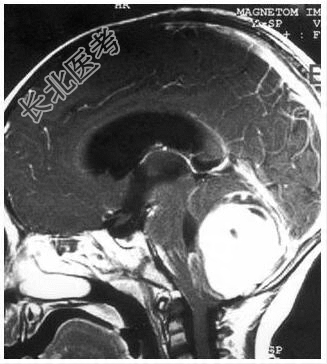

病历摘要:患儿男性,11岁。半年前开始出现行走不稳,常无故跌倒。半月前出现发作性剧烈头痛,伴恶心呕吐。体检:T36℃,P100次/分,R22次/分,BP100/60mmHg,神清,言语较缓慢,双眼外展约不及边,双眼侧视时有小幅度水平眼震。四肢肌力正常,右上肢肌张力较低,坐位姿势不稳,常不自主摇晃,双上肢指鼻不准,行走蹒跚步态,足距扩大,身前倾。患儿行头颅MR检查(见图)